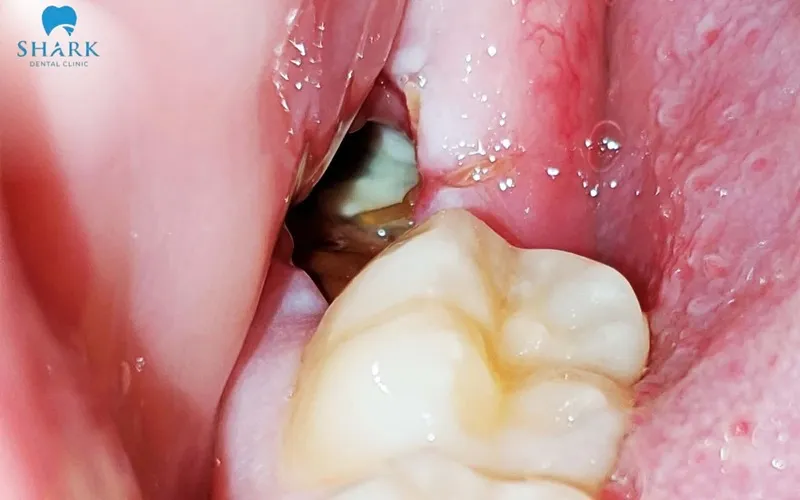

After a tooth extraction, many patients notice a white or pale yellow layer forming over the socket. This appearance is usually part of the normal healing process and is associated with fibrin clot maturation and early granulation tissue formation.

This membrane serves a protective role during the early healing stage. It shields the soft tissue and underlying bone from bacterial invasion in the oral cavity while stabilizing the blood clot, which is crucial for proper tissue regeneration. If the white layer is not accompanied by symptoms such as increased swelling, prolonged bleeding, or severe pain, it is usually a positive sign that the socket is healing properly.

Next, the body begins producing granulation tissue—a type of immature connective tissue rich in capillaries and collagen fibers. Granulation tissue often appears creamy white or light pink and gradually covers the wound surface, replacing the initial blood clot. This is a crucial stage for gum regeneration and socket healing.